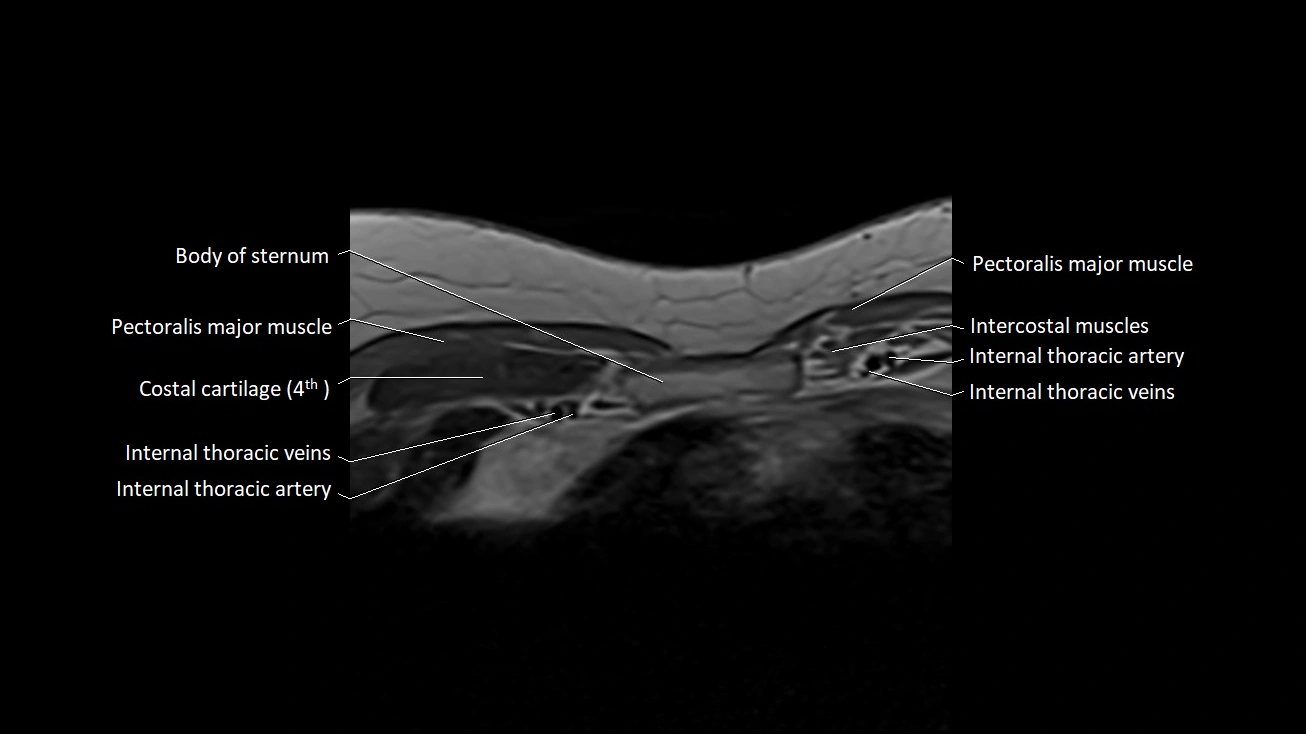

MRI images

image